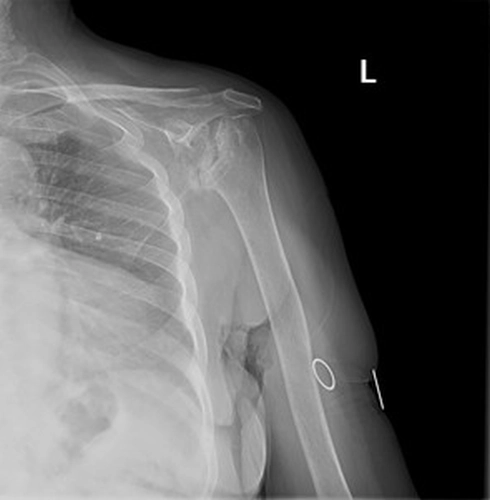

Şikayet:Sol omuzda hareket kısıtlılığı.

Özgeçmiş:10 yıl önce yaygın eklem ağrıları olan hasta RA tanısı almış KS ve MTX kullanım öyküsü mevcut hasta kortikosteroid ile takipli.

Muayene:Sol omuz: Flex: 0-70°, Abd: 0-70°, İstirahatte VAS: 0, Hareket ile VAS:1-2, GYA’de bağımsız. Sistemik tutulum ve organ tutulumu yok. Diğer fizik muayene doğal ellerde deformite yok.

Sol Omuz MRG: Glenoidde kortikal düzensizlikler, lokalize defektif alanlar ve bu düzeyde subkondral milimetrik kistlerin eşlik ettiği medüller hafif hiperintens ödem izlenmektedir. Humerus baş kesiminde medialde de geniş bir alanda defektif görünüm mevcuttur. Buna komşu humerus başında milimetrik kistler ve medüller ödem izlenmektedir.

Humerus başında ve glenoid de osteofitik dejeneratif değişiklikler mevcuttur. Gleno-humeral eklem aralığı anterior inferiorda daralmıştır.Eklem aralığında sıvı miktarında belirgin artış izlenmedi.

Humerusta tüberkülüm majusta milimetrik kist - medüller ödem benzeri sinyal değişikliği dikkati çekmektedir.

Akromioklaviküler eklemde minimal dejeneratif hipertrofi izlenmekte olup eklem aralığı yaklaşık 5 mm ölçülmüştür ve normal sınırlar içerisindedir. Subakromial yağ mesafesi basılıdır. Akromion Tip 2 konfigürasyondadır. Glenoid labrumlar değerlendirilemedi. Biceps uzun başı tendonu normaldir. Supraspinatus tendonunda tendinozis izlenmektedir.

Ön tanıda romatoid artrite bağlı eklem tutulumu, avasküler nekroz, Charcot eklemi (periferik nöropati- servikal radikülopati?) olasılıkları tartışıldı. Hastanın ileri derecedeki eklem kısıtlılığı ve buna bağlı gelişen omuz çevresi kaslarda atrofisi olması sebebi ile artroplastiden fayda görebileceği öngörüldü.